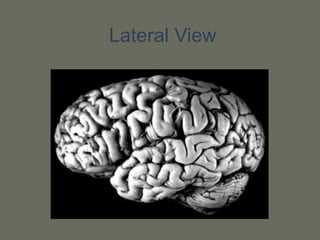

Lateral View

Gyruses and sulci

• Each lobe is composed of gyruses

separated by sulci

Parts of theCentral Nervous System • 2 hemispheres • Brainstem • Cerebellum • Spinal cord

Each hemisphere haslobes: • Frontal lobe • Parietal lobe • Temporal lobe • Occipital lobe • Insular lobe • Limbic lobe